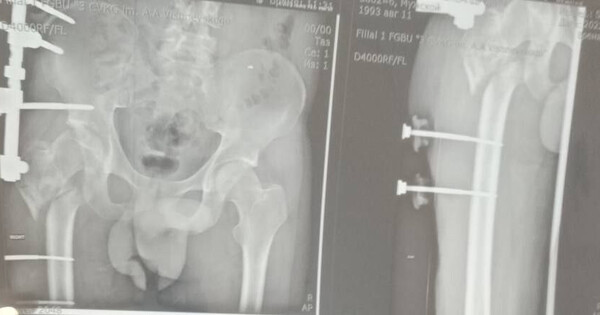

Сержант 1993 года рождения, мобилизованный 25 февраля 2022 года, получил тяжелое ранение правого бедра 28 августа 2022 года под ракетным обстрелом на Херсонщине. За три с половиной года он прошел лечение в десяти госпиталях, включая Москву и Санкт-Петербург. В июле 2024 года боец, награжденный медалью «За отвагу», был уволен по здоровью. Из-за множественных операций и повреждений его правая нога стала короче левой на 8–9 см.

«Требовалось чудо инженерной и хирургической мысли. Чудо произошло 5 марта 2026 года в Луганске. В Луганской республиканской клинической больнице бригада травматологов-ортопедов провела операцию, которая стала финальным аккордом этой долгой истории. Вместо стандартной замены сустава пациенту выполнили сложнейшее вмешательство с использованием ревизионных систем эндопротезирования, в ЛНР такую операцию провели впервые», — рассказала Пащенко.

Хирурги восстановили ось конечности и компенсировали укорочение, работая в рубцово-измененных тканях после множества предыдущих операций, устранив очаги инфекции и «собрав» сустав заново с помощью специальных ревизионных компонентов.